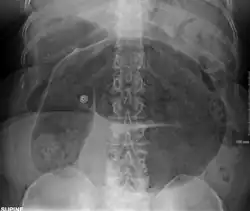

Plain X ray of a cecal volvulus -

CT scan of a cecal volvulus